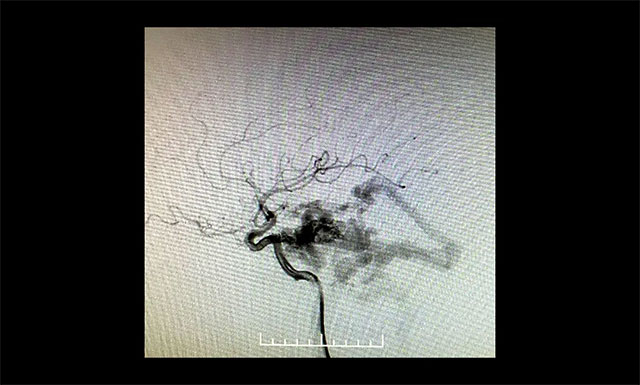

DSA 檢查顯示,左側(cè)天幕區(qū)硬腦膜動靜脈瘺,瘺口血流大,供血來源廣泛,引流靜脈有瘤樣擴(kuò)張。

DSA檢查顯示,左側(cè)天幕區(qū)硬腦膜動靜脈瘺

▲ DSA檢查顯示,左側(cè)天幕區(qū)硬腦膜動靜脈瘺